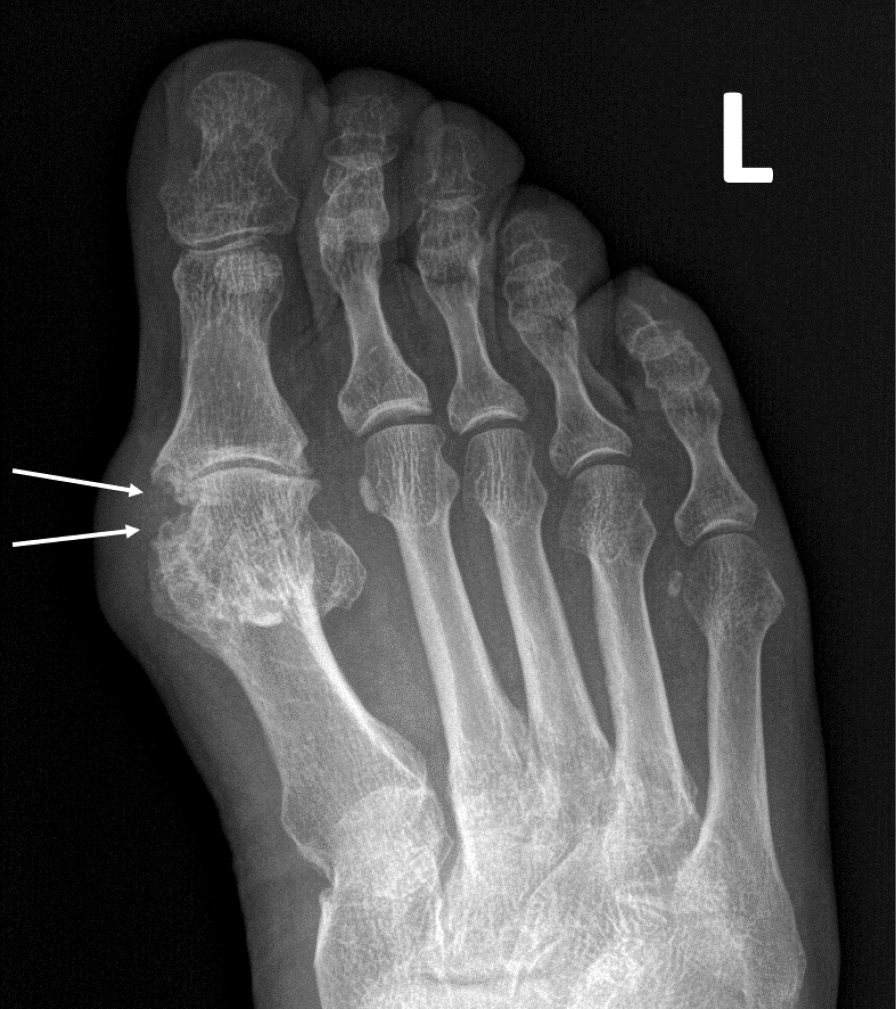

При компьютерной томографии органов грудной клетки данных за «свежие» очаговые и инфильтративные изменения не получено. Увеличения лимфатических узлов подмышечных областей, средостения, корней легких не выявлено. Отмечался усиленный грудной кифоз, обызвествление передней продольной связки, на всем уровне исследования определялись передне-боковые спондилофиты, а также анкилоз большинства реберно-поперечных суставов. По данным рентгенографии кистей (рис. 1, 2) и стоп (рис. 3, 4) диагностированы признаки эрозивного артрита, анкилоз суставов запястья. По данным МРТ крестцово-подвздошных суставов (КПС) определялся неравномерный анкилоз КПС, хрящи по суставным поверхностям неравномерной толщины, примерно на половине протяжении сустава отсутствуют, «суставной промежуток» облитерирован. Неравномерность и нечеткость контура суставных поверхностей за счет множества краевых эрозий справа, единичных – слева, с наличием остеокластоза, в нижнем отделе слева по смежным отделам определяются участки трабекулярного отека, данная находка клинически интерпретирована как двусторонний активный сакроилиит (рис. 5, 6).

Рис. 4. Рентгенограмма левой стопы в прямой проекции. Краевые эрозии суставных поверхностей первого плюсне-фалангового сустава (стрелки), сужение суставной щели. Вальгусная деформация I пальца стопы